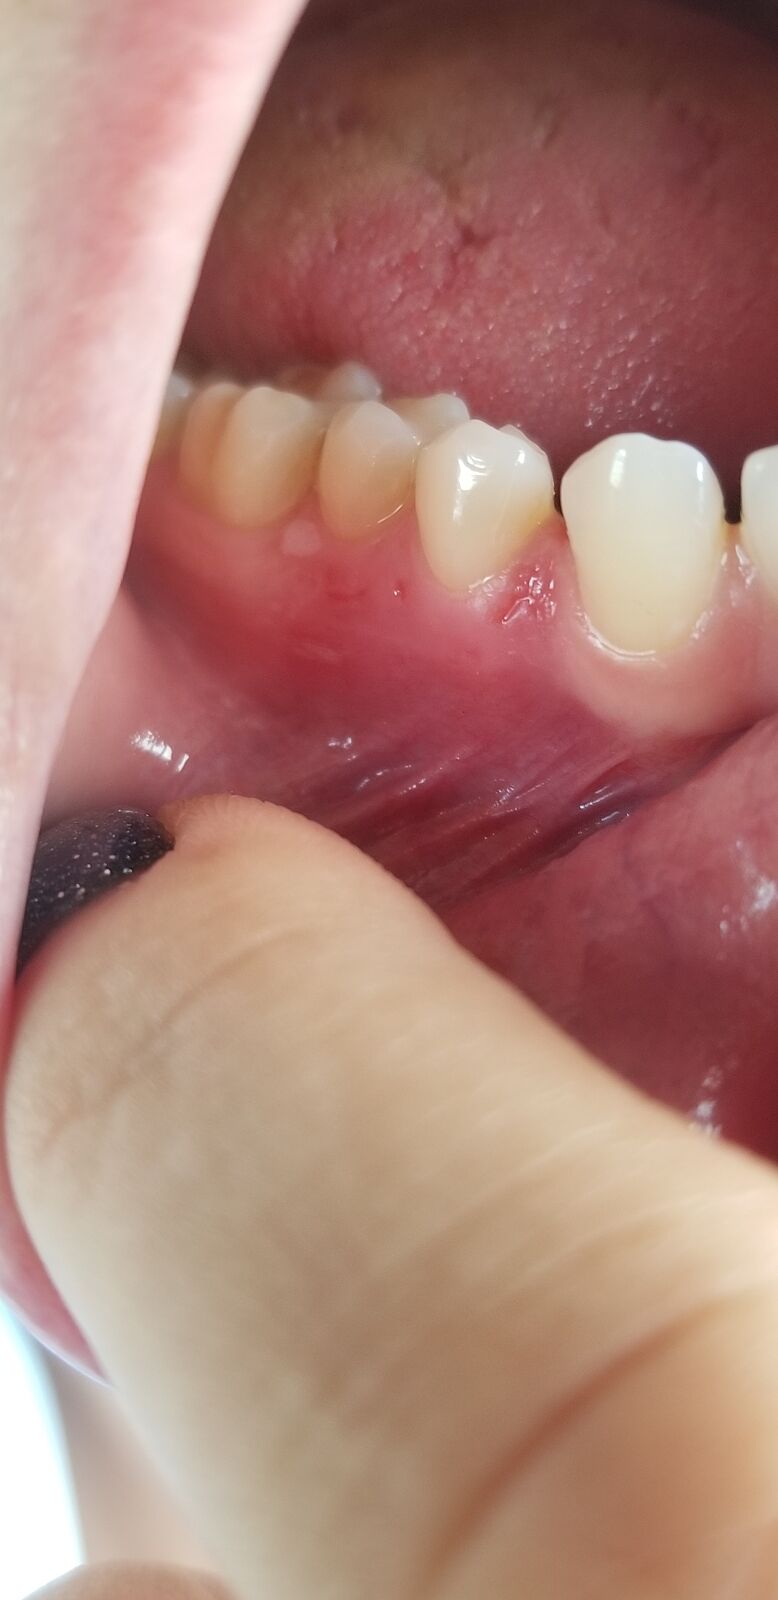

Пятно на десне (фото)

Лет 5 назад появилось белое пятно на десне. Стоматолог сказал, что скорее всего это механическое повреждение от нитки, но лучше убрать. Меня это пятно никогда не беспокоило. За 5 лет оно слегка увеличилось, но не болит и не приносит дискомфорт. Пару дней назад покраснела десна и ниже появилось подобное пятнышко, а вокруг некоторых зубов появилось точечные ранки. Десна немного побаливает. К доктору попасть сейчас не могу. Может у кого-то было подобное, что это может быть?